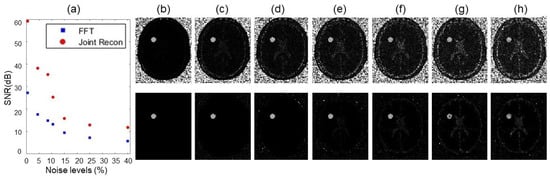

3.2. Numerical Simulations